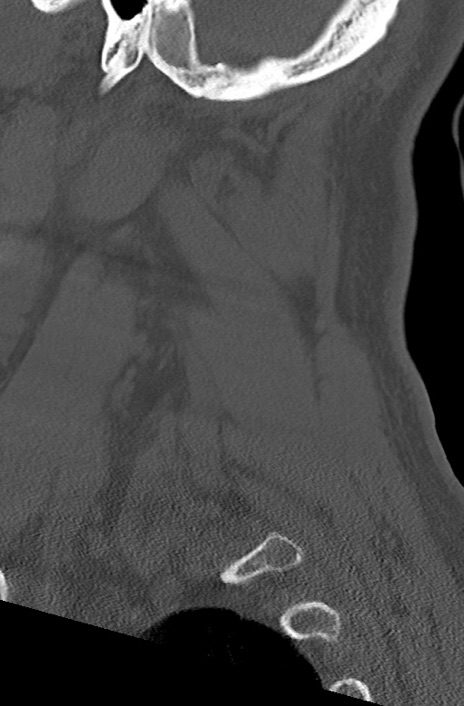

頚椎CT

矢状断像と横断像